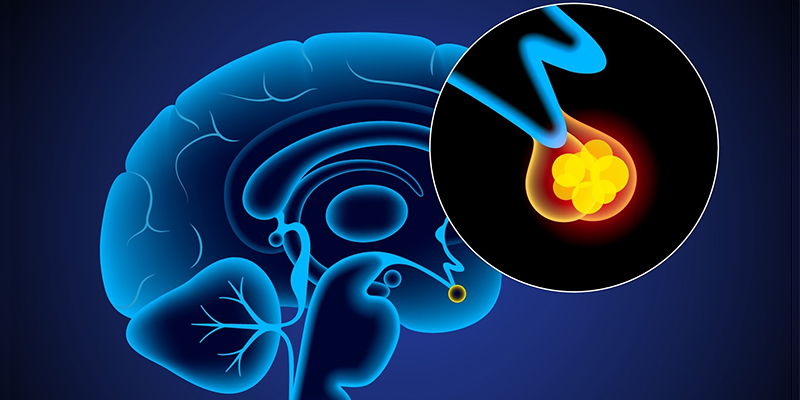

Как работает центр насыщения в гипоталамусе: визуальные иллюстрации